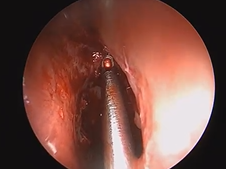

Microdirect Laryngoscopy with CO2 Laser Wedge Excisions for Subglottic Stenosis

- Date : 01/01/2020